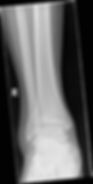

Patient is a 23 year-old female presenting with right ankle pain after tripping over her boyfriend's dog. The patient does endorse alcohol involvement, and has been unable to ambulate on her right leg. She has normal pulses, strength, and sensation distal to her ankle. Images of her ankle are seen below:

Her ankle radiographs are seen below:

1) What is this patient's orthopedic injury?